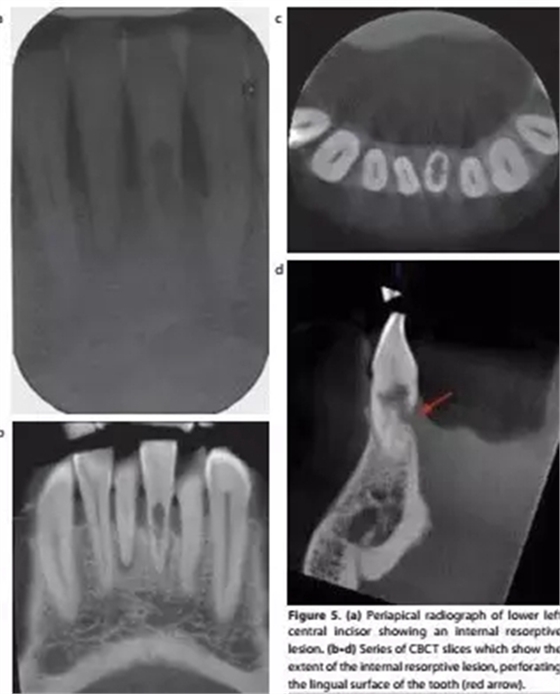

a-根尖片顯示31牙根吸收;b,c,d-對(duì)31的CBCT掃描清楚顯示內(nèi)吸收范圍和程度,舌側(cè)牙根已穿通;

對(duì)于牙根吸收的情況,CBCT能反映病損來(lái)源、位置和進(jìn)展程度,有助于治療方案的制定。例如外吸收一般只能通過(guò)手術(shù)進(jìn)行干預(yù),而內(nèi)吸收則需要根據(jù)程度來(lái)判斷保留價(jià)值。